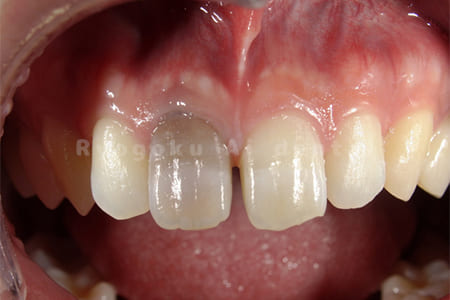

Case07

-

- 原因

- 前歯部失活歯による変色

- 治療内容

- 根管治療ならびに、ダイレクトボンディング、ブリーチング

- 治療費用

- 198,000円

前歯の変色と歯が欠けているのが気になるとのことでご来院された患者様です。治療後の仕上がりにも満足されていました。